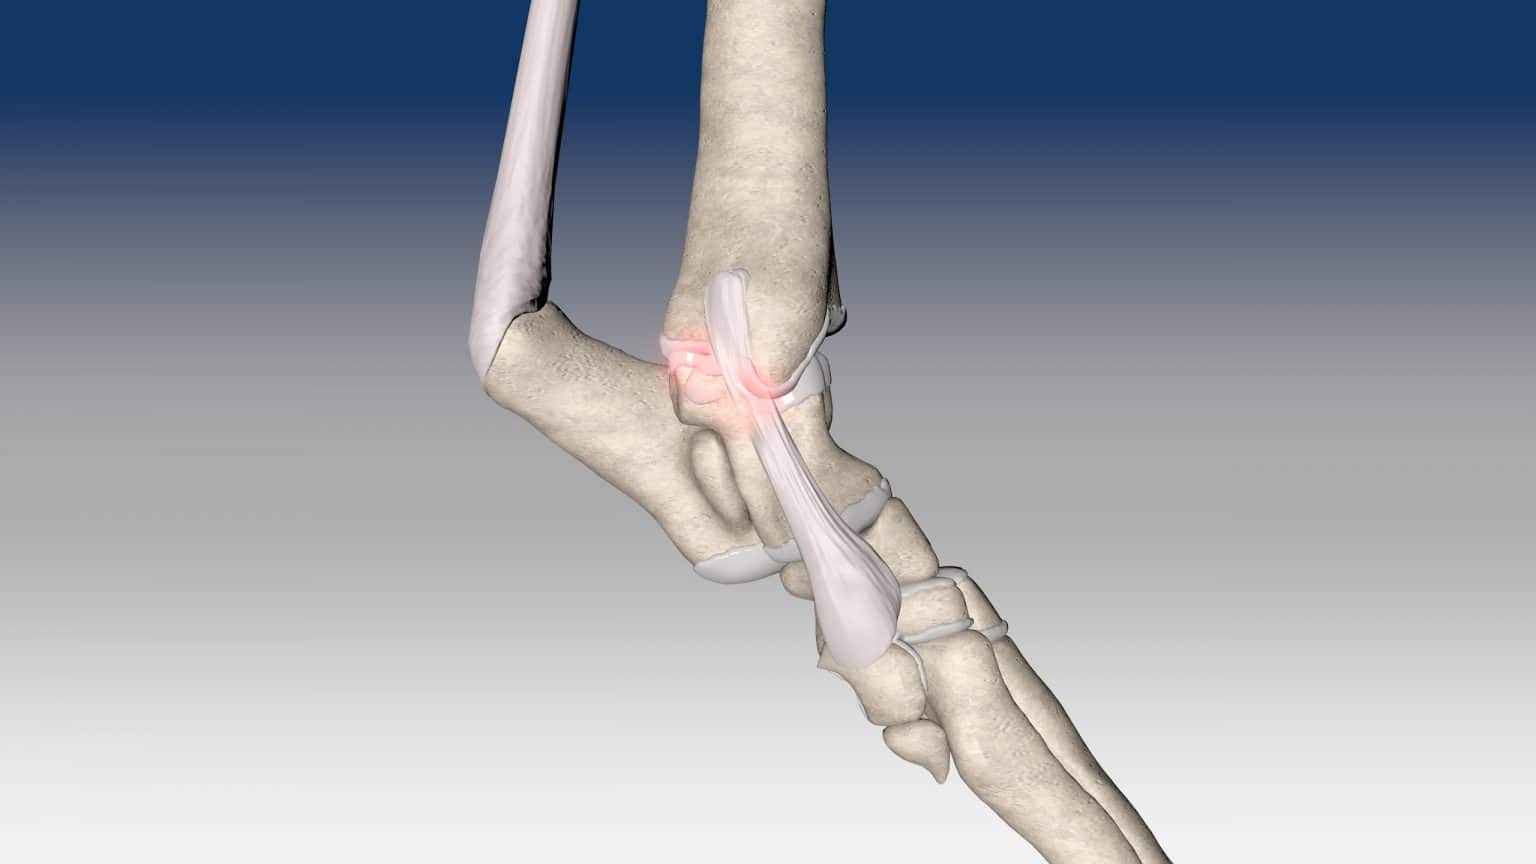

Reconstruction of tarsal medial collateral ligament